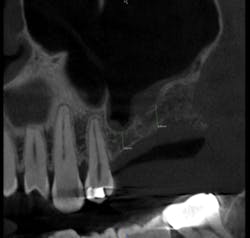

After reviewing the image, we performed a sinus lift procedure and placed two implant fixtures. A follow-up CBCT volume was taken one month later to check for overall healing, graft containment and sinus health (figs. 4, 5). The scan demonstrated normal healing from all perspectives. The patient went on to have the implants successfully restored once integration was clinically confirmed.

Figure 4: